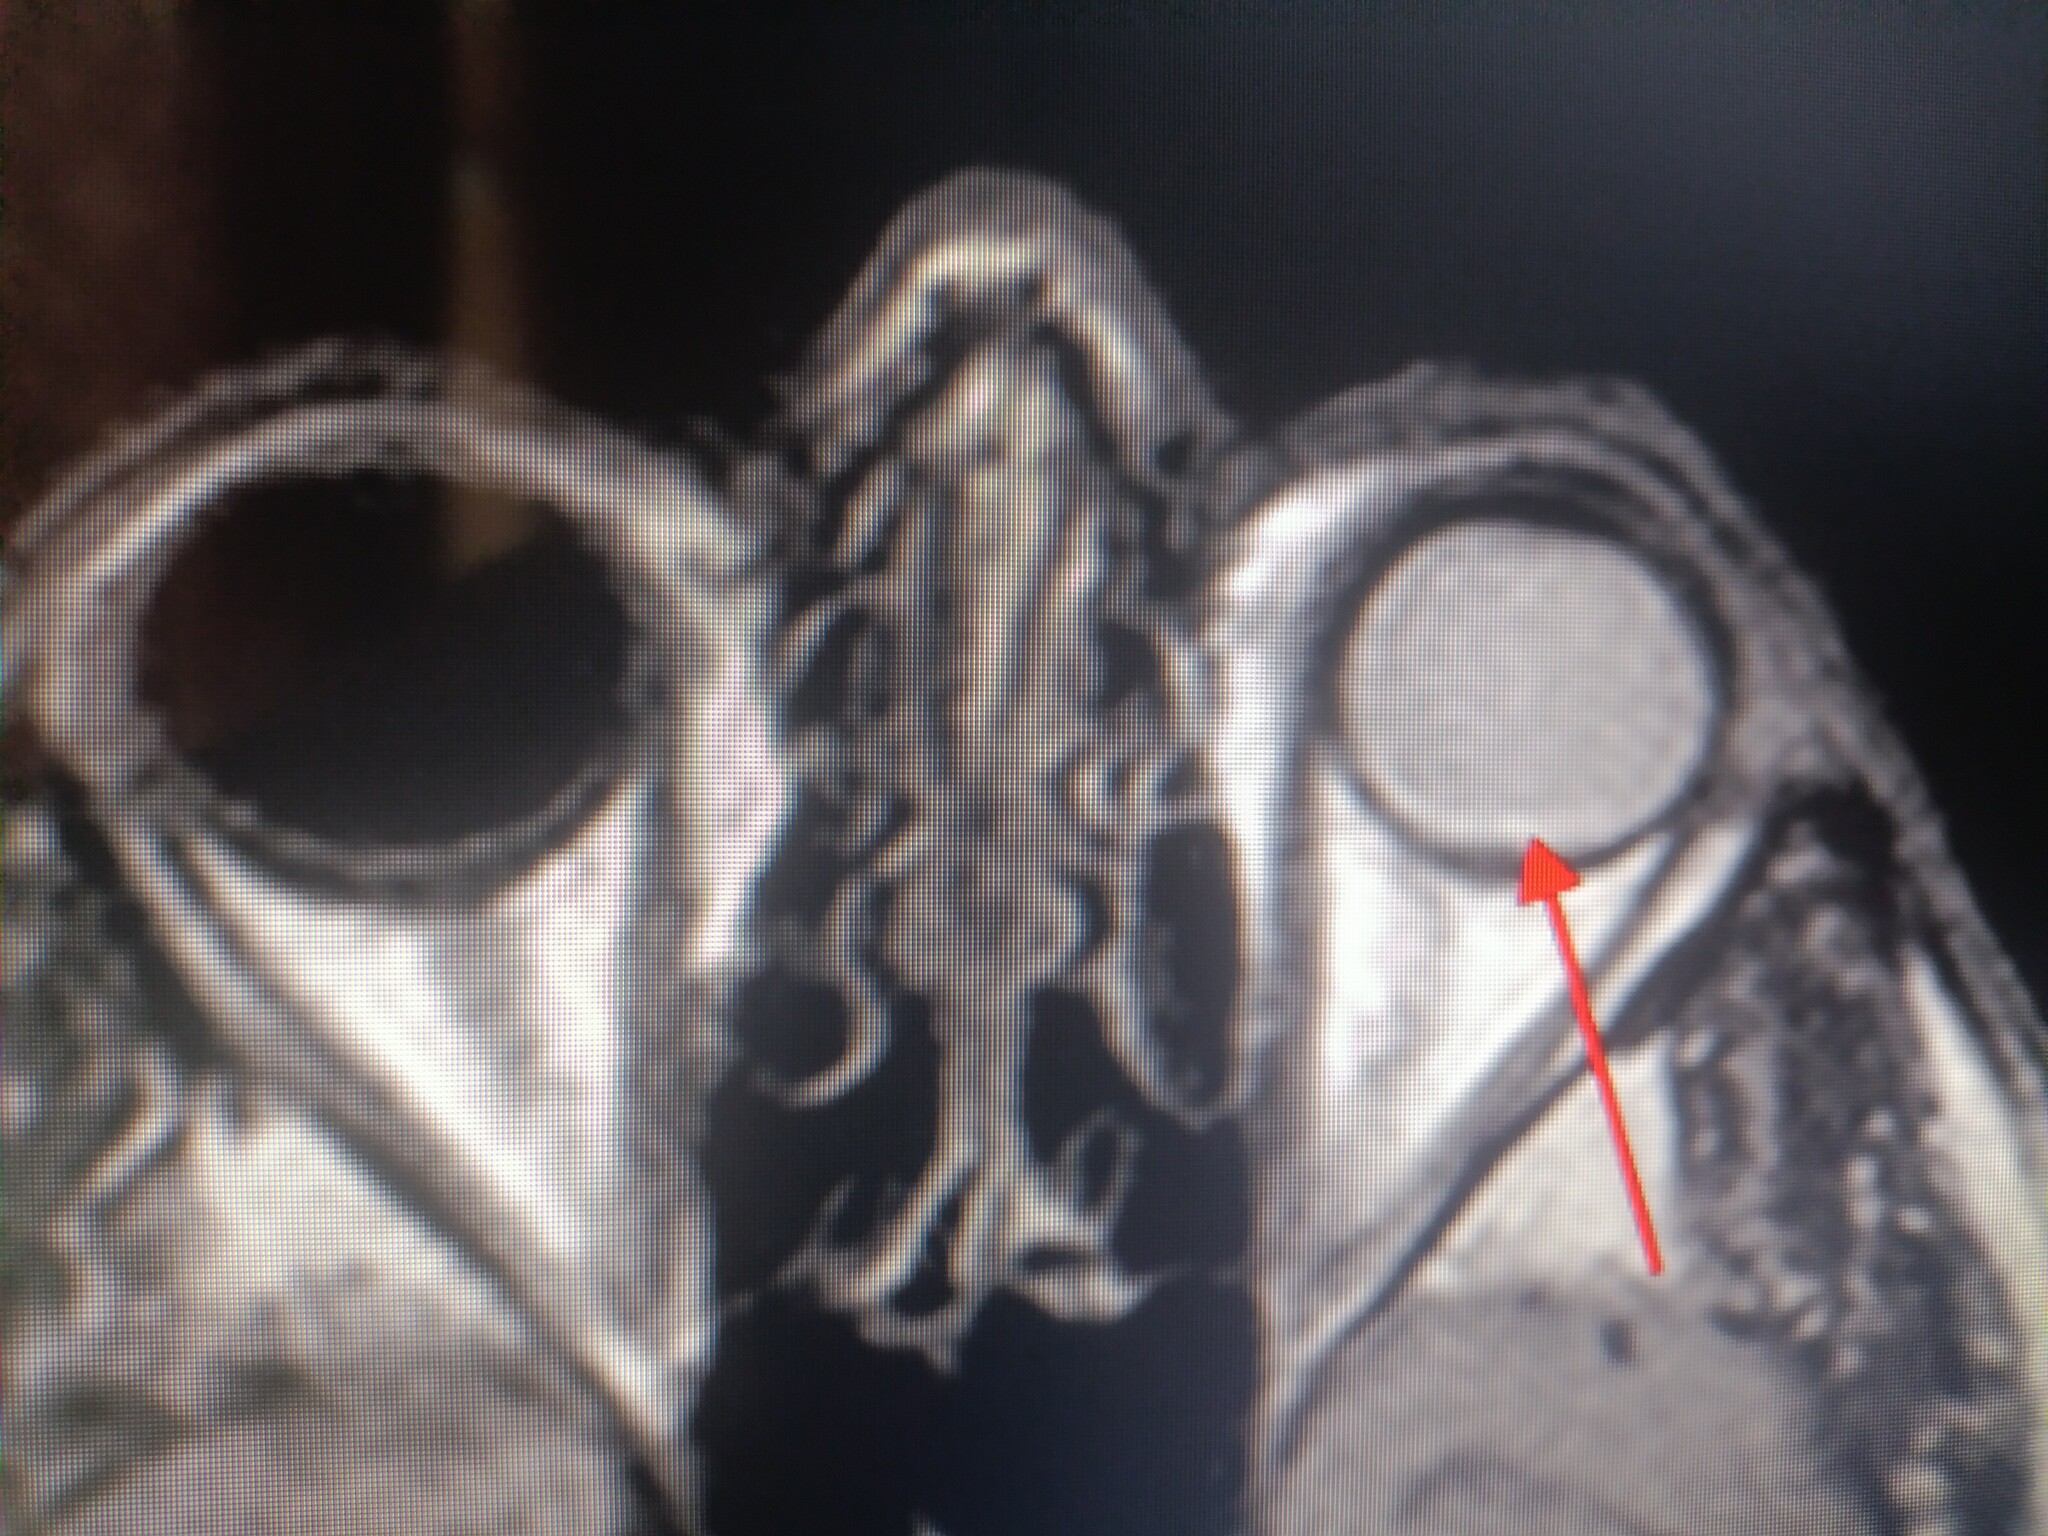

Оно конечно да, только вот есть и те, кто насобирал на лечение ретинобластомы в Швейцарии и успешно сохранил даже остроту зрения. А тем, которые не насобирали, просто вырезали глаза в той самой районной больничке